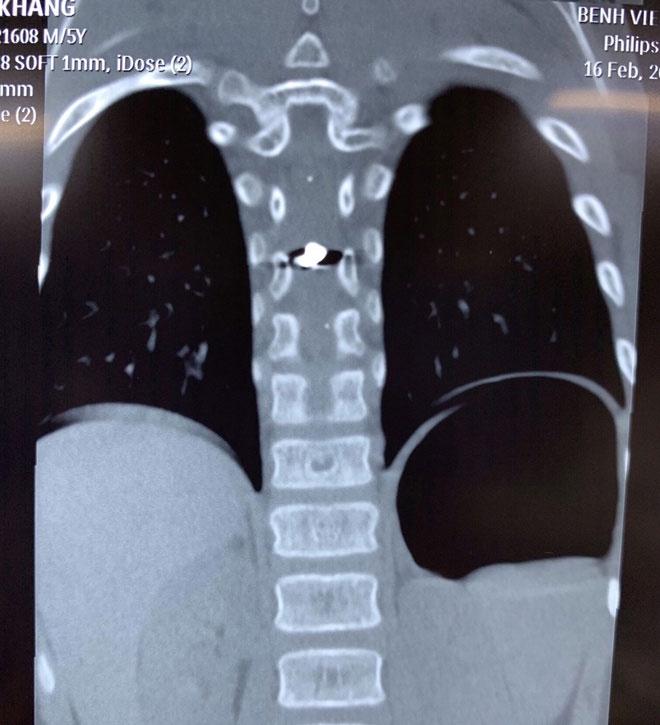

Hình ảnh viên đạn trong tuỷ sống bệnh nhi. Ảnh: BVCC.

Kết quả trên phim CT Scan cho thấy viên đạn chì xuyên vào tuỷ sống ngực của bệnh nhi.